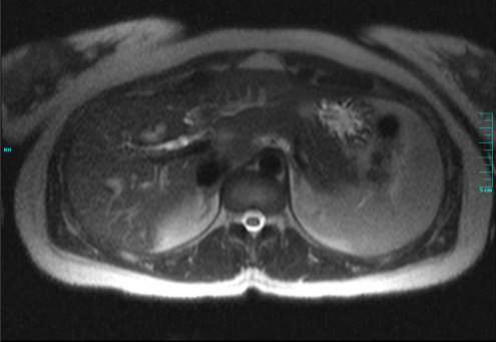

Figure 1A, Figure 1B

Figure 1A and 1B – MRCP showing the beading of the intrahepatic biliary tree with high grade strictures of the right and left hepatic ducts, suggestive of Primary Sclerosing Cholangitis

A 23-year-old Albanian woman presented with two days of severe, intermittent epigastric and right upper quadrant abdominal pain. The pain had been ongoing over the past year but worsened two weeks prior to admission. She admitted to dark urine and light-colored stools but denied diarrhea, constipation, blood in the stool, fevers, chills, night sweats, or weight loss. She was afebrile, normotensive with a normal heart and respiratory rate. She was noted to be in moderate distress and ill-appearing with scleral icterus. Abdominal examination revealed mild epigastric tenderness without guarding or rebound. Complete blood count was within normal limits with a normal platelet count as well as a normal INR and prothrombin time. Liver panel demonstrated a total bilirubin of 4.5mg/dL, direct bilirubin of 2.8mg/dL, alanine aminotransferase 354mg/dL, aspartate aminotransferase 174mg/dL, and alkaline phosphatase 118mg/dL. Hepatitis serologies were negative. Her CA 19-9 level was elevated to 143U/ml. Abdominal ultrasound revealed multiple gallstones within the dependent portion of a normal gallbladder, the largest measuring 0.6cm, and a prominent distal common bile duct (CBD) within the pancreatic head. Magnetic resonance cholangiopancreatography (MRCP) revealed beading of the intrahepatic biliary tree with high grade strictures of the right and left hepatic ducts, suggestive of Primary Sclerosing Cholangitis (PSC), cholelithiasis, and a small stone in the distal CBD with mild dilatation of the CBD and the intrahepatic biliary ducts [figure 1A and 1B]. She underwent ERCP where brushings were obtained from the strictured portions and sent for cytology. Additionally, a sphincterotomy was performed and stones and sludge were extracted from the bile ducts. A 7Fr x 9cm straight plastic stent was placed into the right intrahepatic system and a 7Fr x 15cm straight plastic stent was placed into the left intrahepatic system, [figure 2] though this stent was seen extending slightly within the duodenal lumen. The evening after the procedure, the patient developed an episode of vomiting and abdominal pain however her physical examination appeared stable from prior examinations. Labs obtained at that time revealed mildly elevated lipase with a mild leukocytosis so her symptoms were attributed to post-ERCP pancreatitis and she was made nil per os (NPO) and treated with intravenous fluids and analgesia. Her nausea and epigastric pain subsided by the next morning but she subsequently developed right lower quadrant abdominal pain. She was scheduled to undergo laparoscopic cholecystectomy the following day so the decision was made to also perform laparoscopic evaluation for the right lower quadrant pain and possible acute appendicitis, during the procedure. The laparoscopy revealed significant bilious fluid in the right paracolic gutter associated with inflammation. Upon further evaluation, the biliary stent was noted to be eroding through the duodenum at the junction of the second and the third portions [figure 3]. The duodenal perforation was repaired and reinforced with a Graham patch. Due to the extensive inflammation, a right hemicolectomy with ileocolic anastomosis was performed with copious lavage of the peritoneal cavity. The patient did well postoperatively and was discharged on the sixth postoperative day. Cytology from the biliary stricture brushings demonstrated reactive cells without evidence of malignant cells. Pathology from the surgical specimens demonstrated a segment of small and large intestine with marked acute and chronic inflammation involving peri-intestinal fat, with abscess, hemorrhage, fat necrosis and fibrinopurulent serosal exudates. The margins of the resection appeared viable.